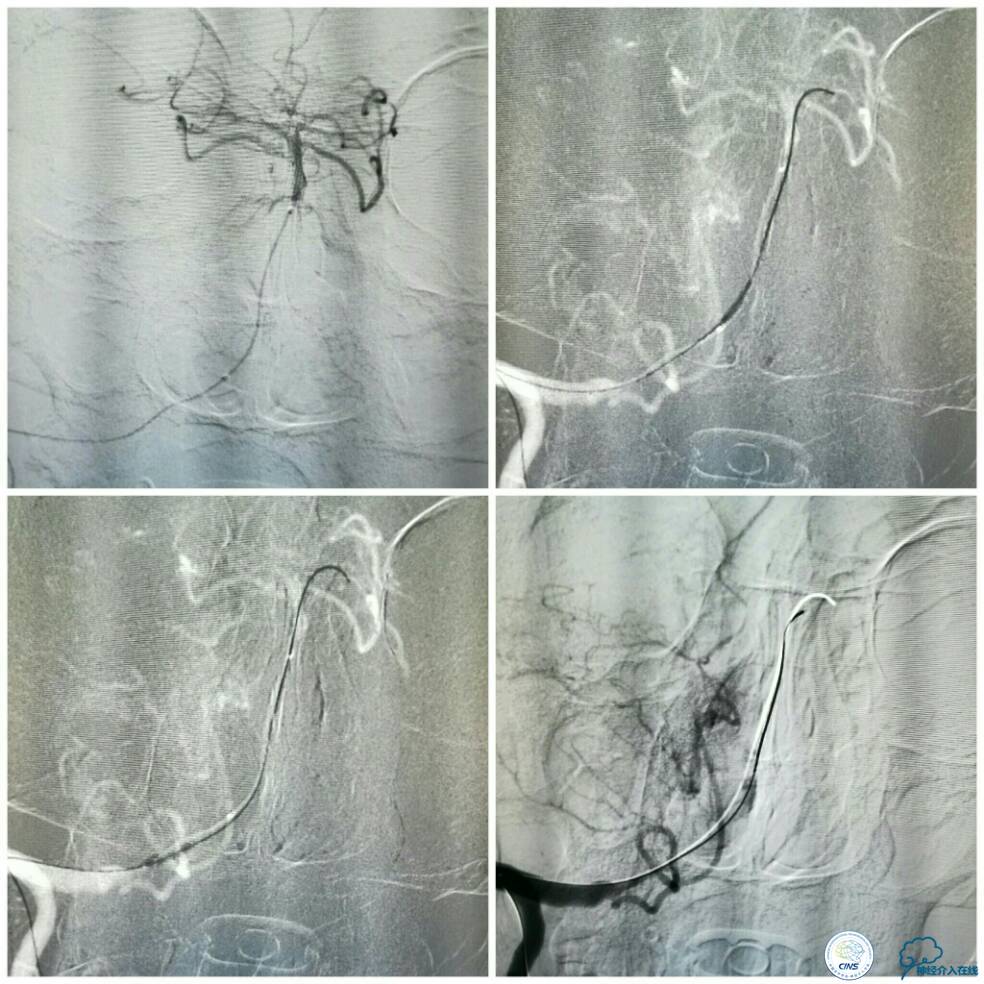

此时经6F导引导管和放置在左椎动脉V1段的5F椎动脉造影导管行双路径图,以显示椎基底动脉系统。选用Apollo球囊扩张支架(2.5 mm×13 mm 3枚,3.0×8 mm 1枚)自闭塞远端至近端依次释放支架,两个支架间重叠约2 mm(图10)。

图10

支架释放过程中给予替罗非班3 ml/h静脉持续泵入,以预防急性血栓形成。最后一枚支架释放完毕后造影显示右椎动脉V4段再通,支架贴壁良好,前向血流TICI分级3级,左椎动脉V4段逆向显影(箭头)(图11)。

图11